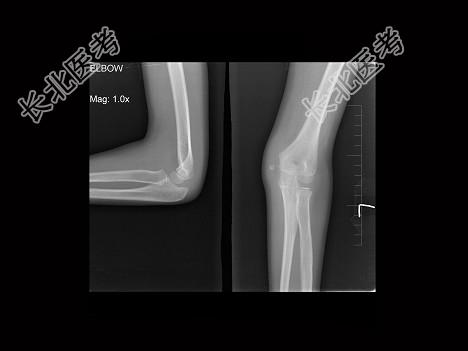

- 单项选择题男,9岁, 左肘外伤,结合图像, 最可能的诊断为 ( )

A、左肱骨内上髁骨骺1度分离

B、左肱骨内上髁骨骺2度分离

C、左肱骨内上髁骨骺3度分离

D、左肱骨内上髁骨骺4度分离

E、左肱骨内上髁骨骺5度分离